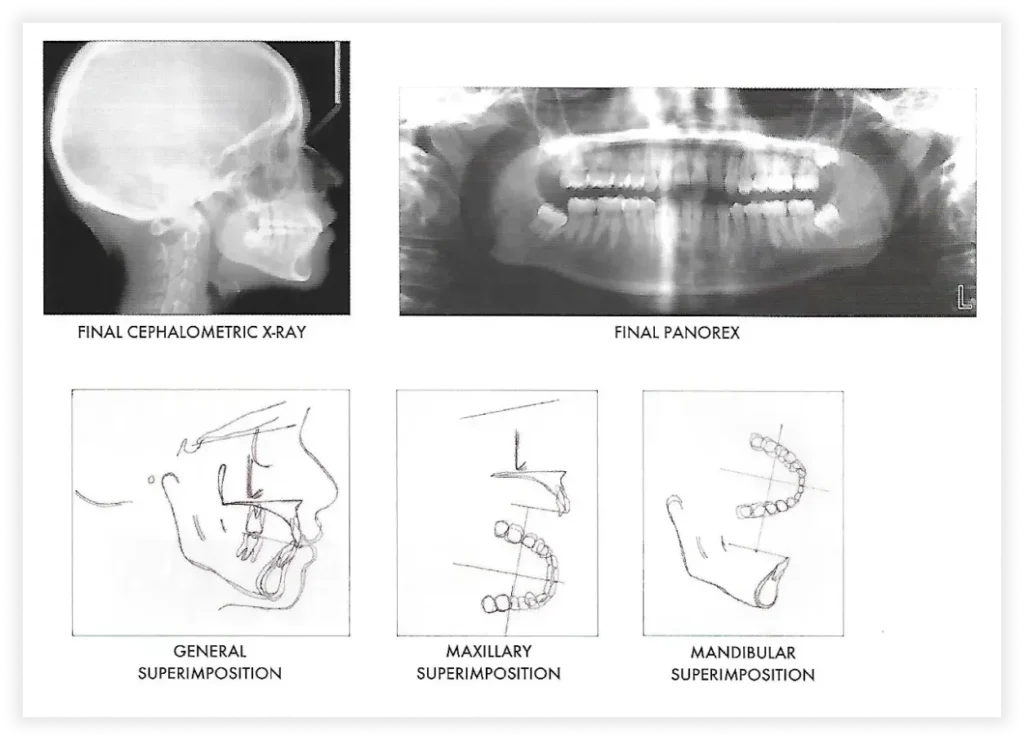

Case #2

Initial Photos

Final Photos